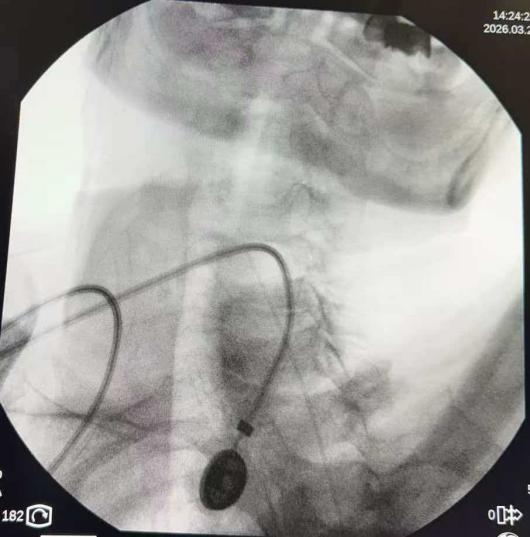

其运行机制可类比军事行动中的“精准打击”,通过微创手术,将一个可储药的泵体植入患者腹部皮下,并将一根纤细的导管精准置入蛛网膜下腔(鞘内)。药物不再经过胃肠道吸收或血液循环,而是直接作用于脊髓和大脑的疼痛信号“指挥中枢”。

在邹定全主任精准操作及邵阳市中医医院疼痛团队的密切配合下,手术过程顺利。术后,患者的疼痛评分从术前的重度疼痛(8-9分)迅速降至轻度或无痛状态(0-2分)。